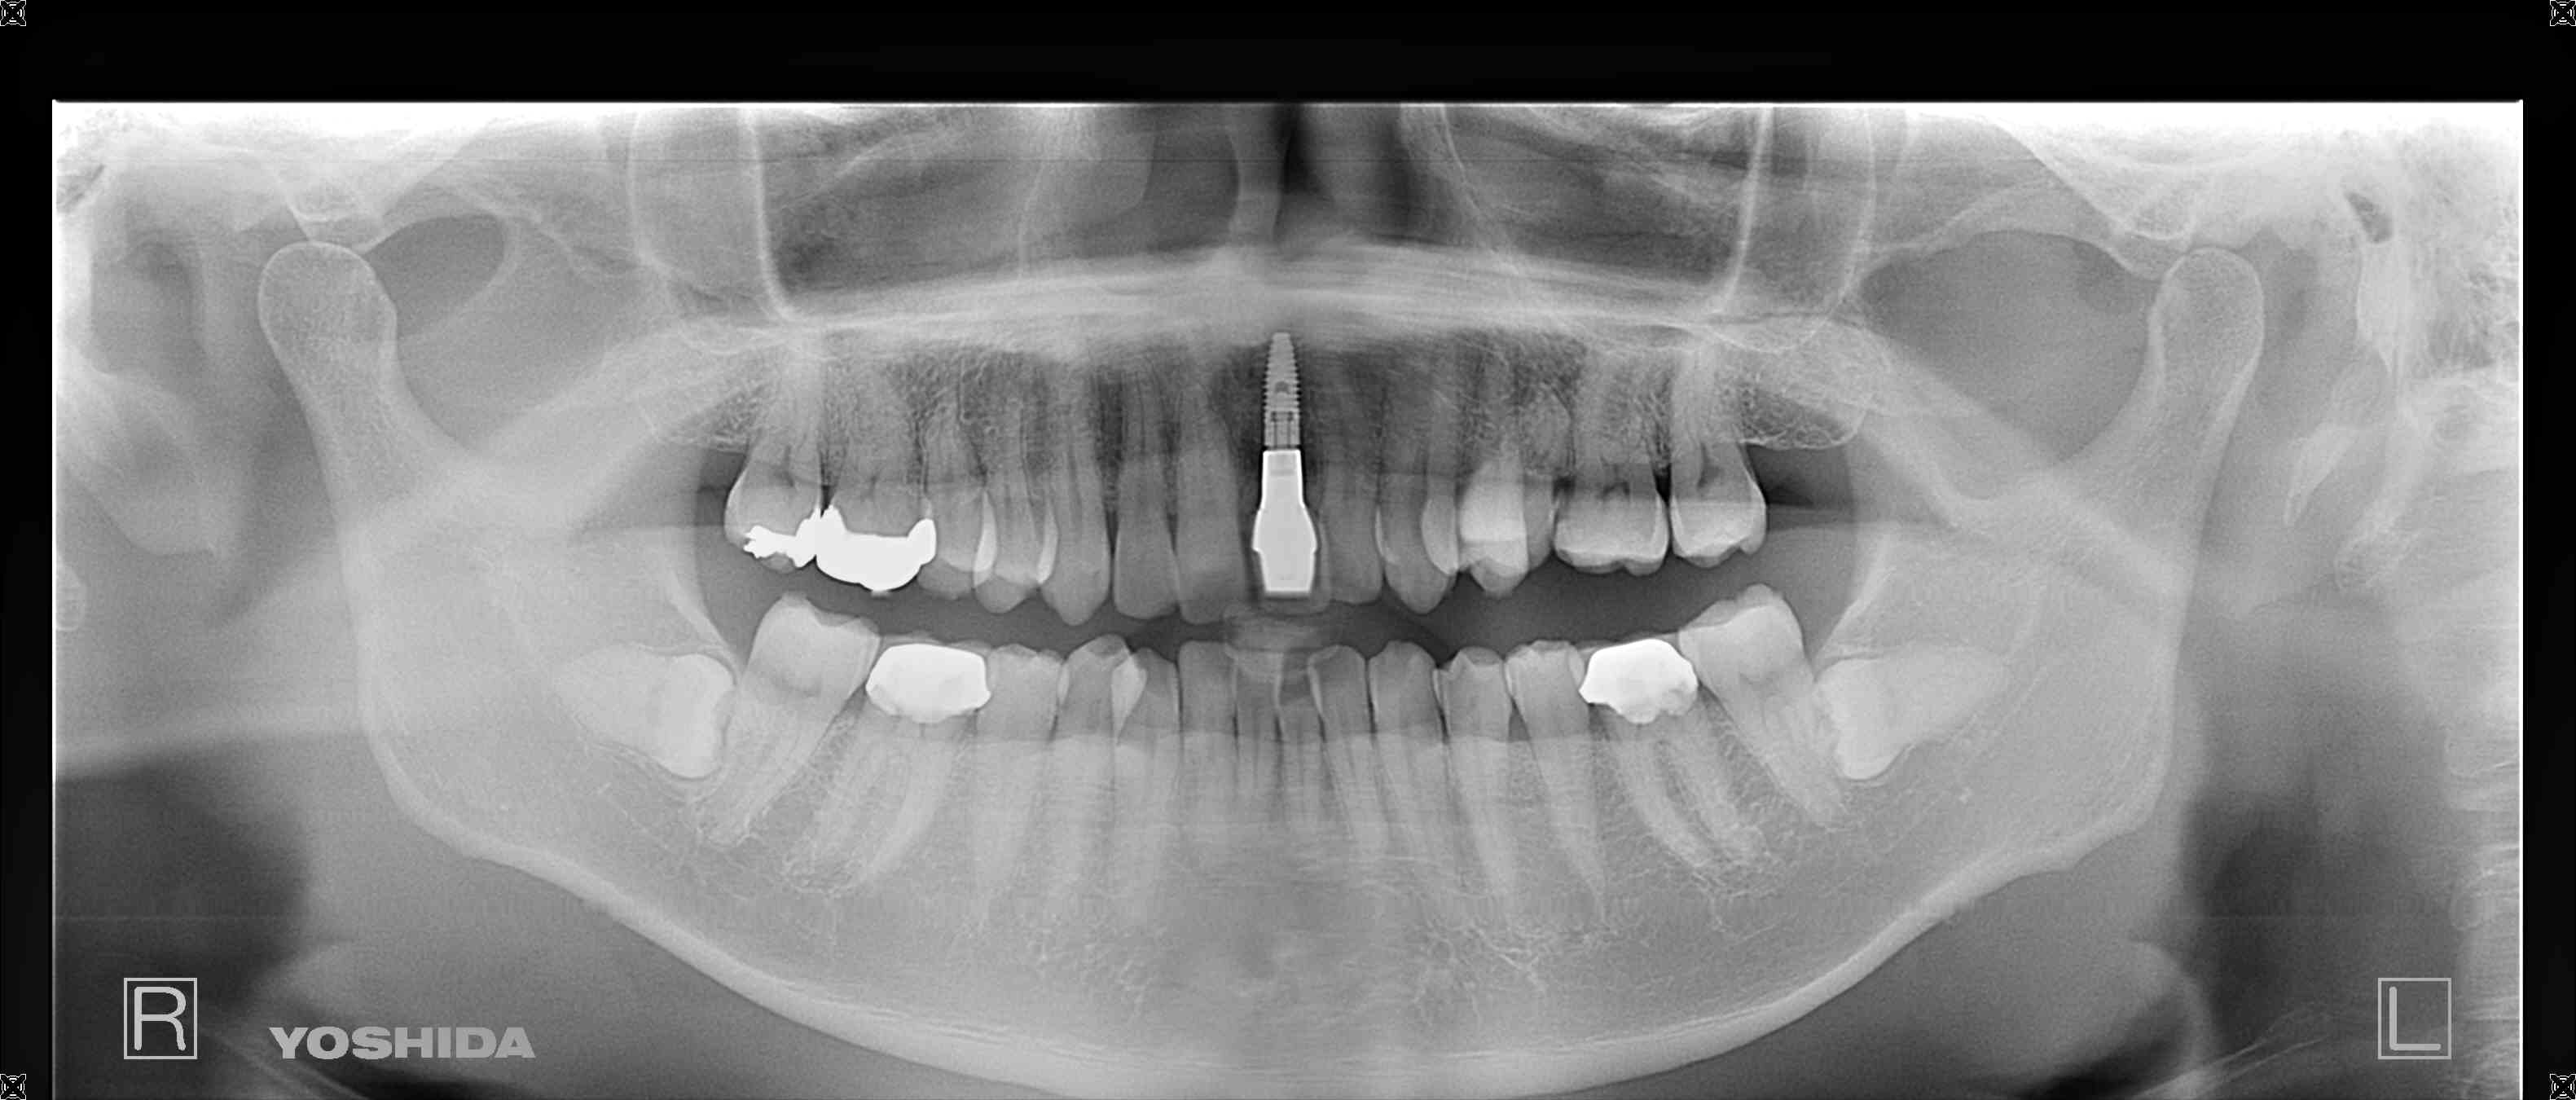

下の写真は、治療完了後の状態です。